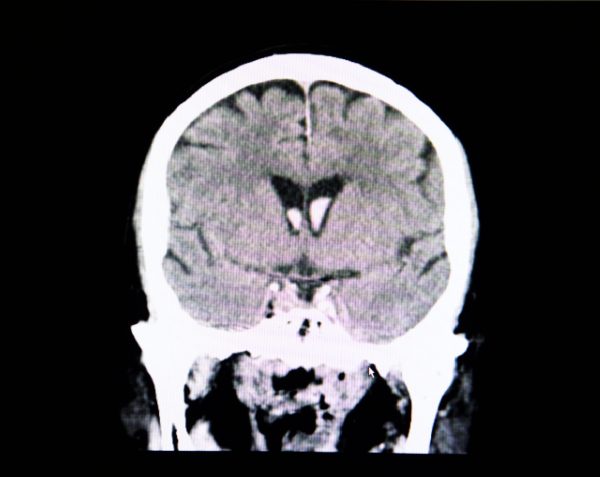

Salud y vida Hospital Angeles Health SystemCraneotomía | ¿En qué consiste?La craneotomía es una cirugía que permite acceder al cerebro para tratar enfermedades. Conoce en qué consiste, sus beneficios y riesgos.Compartir: